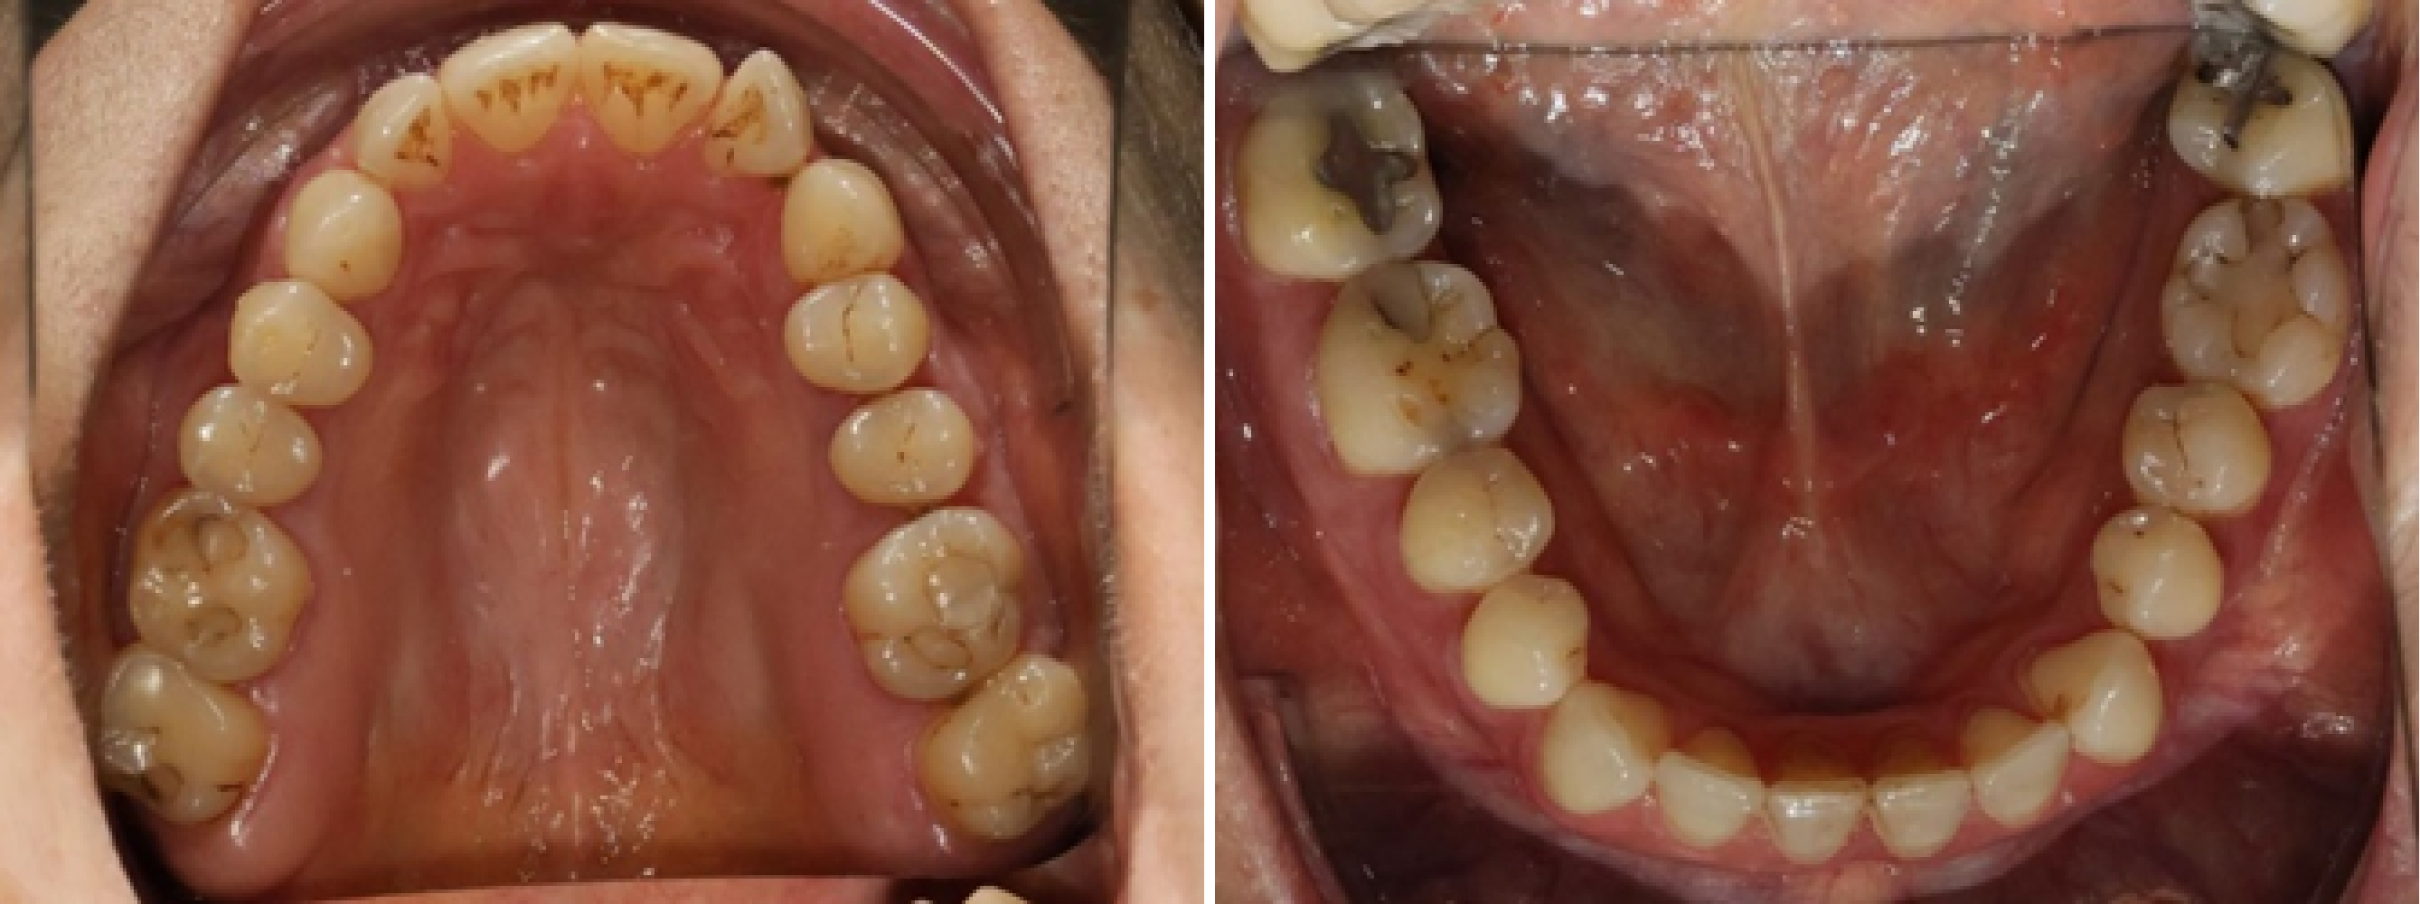

- • Des photographies